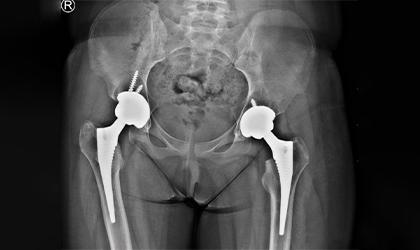

Bilateral Knee Replacement Case Study

Independent, Pain-Free, Walking

This 68 year old lady has a condition called protrusio where the socket becomes weak and protrudes into the pelvis